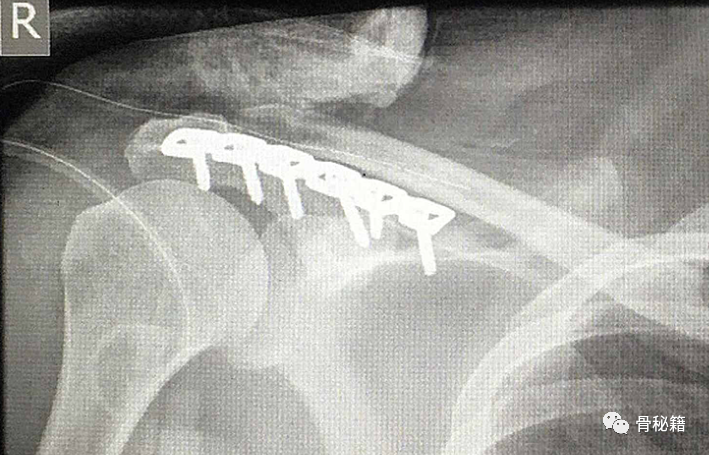

肩峰粉碎骨折,采用钢板螺钉固定,完成悬吊复合体的稳定

肩峰骨折 移位明显,采用钢板固定